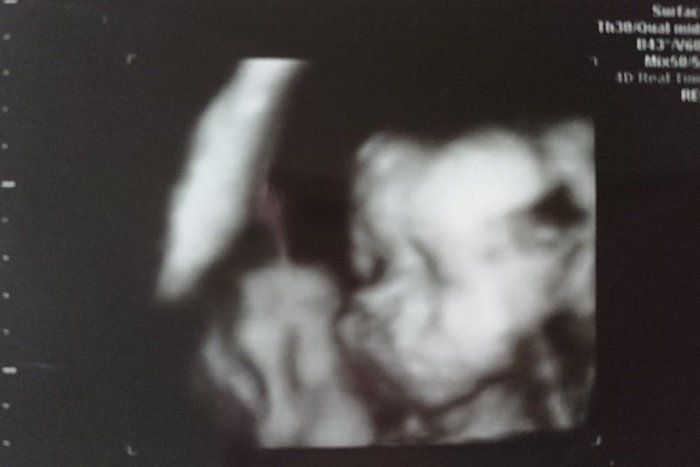

つぼいみきさんの妊娠27週目のエコー写真 初めての4Dエコーに成功

推定体重1000g

初めて4Dエコーに成功! 手が顔の前にあるけど、ちゃんとお顔を見せてくれました。目、鼻、口がこんなにもはっきりと映るのかと驚きました。「鼻はパパ似!? 口はママ似!? 」と話が盛り上がりました。とにかくかわいくて愛おしくて仕方がありません。この日の検診で血糖値が引っかかってしまい、再検査となりました。ここ最近はとにかく果物が食べたくて仕方なく、「その影響もあったのかな? 」と反省しました。